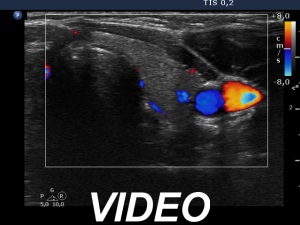

Ultrasonography. The thyroid was echonormal. There was a heterogeneous nodule in the right lobe. The lesion contained roughly equal proportions of echonormal and moderately hypoechoic portions. The nodule had a thin halo and presented perinodular blood flow.